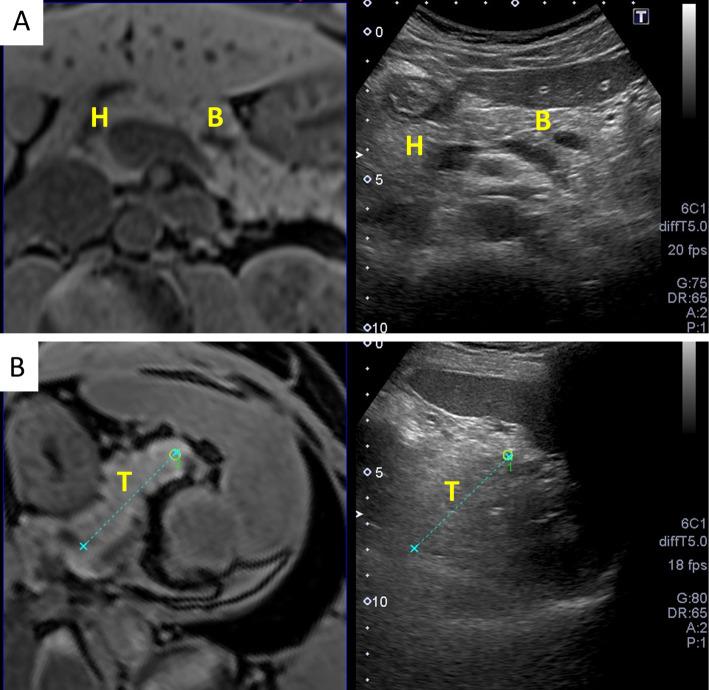

Objective Abdominal ultrasonography (AUS) is used to screen for abdominal diseases owing to its low cost, safety, and accessibility. However, the detection rate of pancreatic disease using AUS is unsatisfactory. We evaluated the visualization area of the pancreas and the efficacy of manipulation techniques for AUS with fusion imaging. Methods Magnetic resonance imaging (MRI) volume data were obtained from 20 healthy volunteers in supine and right lateral positions. The MRI volume data were transferred to an ultrasound machine equipped with a fusion imaging software program. We evaluated the visualization area of the pancreas before and after postural changes using AUS with fusion imaging and assessed the liquid-filled stomach method using 500 ml of de-aerated water in 10 randomly selected volunteers. Patients This study included 20 healthy volunteers (19 men and 1 woman) with a mean age of 33.0 (21-37.5) years old. Results Fusion imaging revealed that the visualization area of the entire pancreas using AUS was 55%, which significantly improved to 75% with a postural change and 90% when using the liquid-filled stomach method (p=0.043). Gastrointestinal gas is the main obstacle for visualization of the pancreas. Conclusion Fusion imaging objectively demonstrated that manipulation techniques can improve pancreatic visualization.